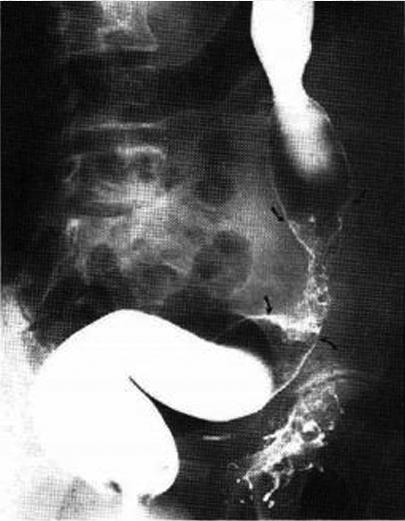

Maladie de Crohn ileo-colique

: Lesions nodulaires sur le colon transverse et

ceaco-ascendant Image radiologique de

lavement baryte en double de contrast |

Aspect d'ulceration aphtoides sur

le colon transverse et sigmoide ( fleche noire ) ;

|

Image stenose et lesion

ulcere en fissure de ileon peut voyait si net

sur le lavement baryte en double de contrast du

colon . |